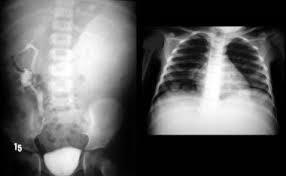

Glomerulonephritis (left) inflammatory disease of the capillary loops of the renal glomeruli (within nephrons) AKA bright disease Commonly developed after streptococcal infection due to antigen-antibody deposited in glomerulus Commonly causes underdeveloped kidneys Characterized by hypertension Symptoms: nausea, malaise, and joint pain Lab test show: increase in albumin, BUN, and creatinine CXR has pulmonary infiltrates Radiographic Appearance: can lead to renal failure, if chronic it leads to fibrosis, leading to the kidney shrinkage, scarring, and shrinkage but initially the kidneys are enlarged due to inflammation

Pyelonephritis (Right) Inflammation of the kidney and renal pelvis Acute: escherichia coli invades the renal tissue, commonly enters the kidney through retrograde from the bladder of through blood Chronic: chronic reflux occurs of infected urine from the bladder into the renal pelvis More common in females symptoms: flank pain, bacteriuria, pyuria, dysuria, nocturia, and increased frequency of urination Acute: calyces are enlarged, blunting of calyces Chronic: decreased kidney size with destruction and scarring due to fibrosis